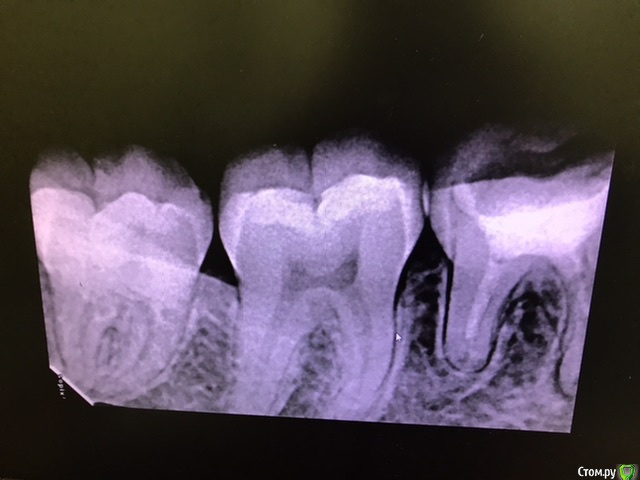

ho4u-vra4a Опубликовано 23 марта, 2020 Поделиться Опубликовано 23 марта, 2020 здравствуйте! обращаюсь к специалистам! пишу своим непрофессиональным языком, не судите строго.6 дней назад обратилась на перелечивание каналов с гранулемой ( или что это точно - я не знаю).46 зуб. мне установили коффердам, вскрыли старую пломбу, сверлили разными приборами, прочищали каналы, промывали хлоргексидином и гипохлоритом.весь процесс мучения длился полтора часа. в итоге мне запломбировали каналы с кальцием. поставили внутрь временную пломбу, а сверху еще закрыли постоянной. сделали рентген и отпустили домой. начинала я всю эту процедуру без анестезии, но в процессе все-таки попросила сделать её, так как было больно. и после того, как мне установили световую пломбу у меня уже начали боли в зубе усиливаться, а когда отошла заморозка - боли были невыносимые. врач сказала, что будет болеть, посоветовала пить ибупрофен.но я не ожидала, что боли будут настолько острые. к слову, мне не помогали ни ибупрофен, ни найз. я протерпела несколько дней, т.к врач не работала пару дней, и потом поехала к врачу снова. на мою просьбу сделать рентген - мне сказали, что я там все равно ничего не увижу. ок. они вскрыли мою световую пломбу, убрали все из зуба, включая пасту с кальцием, снова промыли все хлоргексидином, поставили туда внутрь так же хлоргексид и метронидазол. закрыли временной пломбой. боль во время данной процедуры прошла, но затем через несколько часов появилась снова. на следующий день я созвонилась с врачом, она сказала, что тогда придется пить антибиотики, т.к. уже началось воспаление и мой зуб "не прошел на герметичность". от предложенных антибиотиков я отказалась, т.к. у меня на них сильная аллергия. но указала, на какие группы антибиотиков у меня нет аллергии. врач сказала, что подумает и пригласила снова на осмотр на следующий день. в тот же день я открыла для себя кеторол, который помог заглушить острую боль. но появилось чувство распирания и как будто мне кололи в кость чем-то. на следующий день ( то есть уже сегодня) меня опять осмотрели, опять промыли каналы, опять поставили временную пломбу. через два часа я стала пить теплый ромашковый чай, и от него у меня снова острая боль. что мне делать? какие могут быть ошибки или может быть проблема в моем зубе и иммунитете? почему болит постоянно зуб, если причина боли должна уходить? прикрепляю рентген до и рентген после первого лечения. также есть КТ до перелечивания, вдруг кто-то заинтересуется. спасибо! 1 Ссылка на комментарий